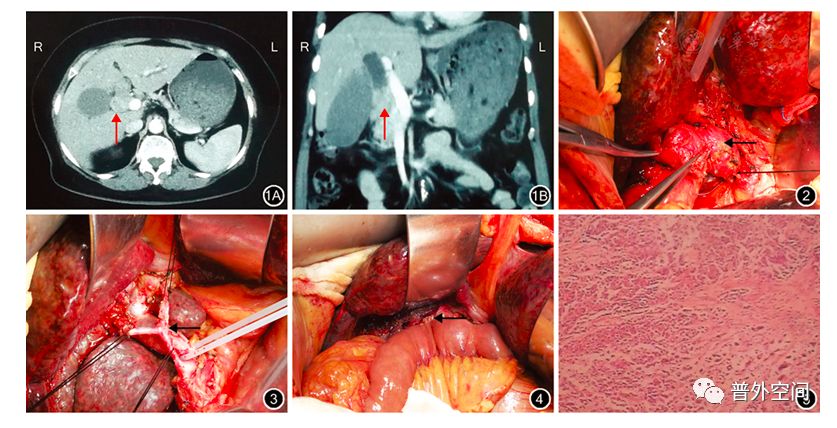

图1:腹上区增强CT检查结果 1A:横断面显示胆总管上段及肝总管管壁增厚,胆管扩张(↑);1B:冠状面清晰显示肿瘤位置(↑)

图2:术中见胆总管上段肿瘤(←)

图3:淋巴结清扫+肝十二指肠韧带骨骼化(←)

图4:肝总管-空肠Roux-en-Y吻合(←)

图5:术后肿瘤病理学检查结果示胆总管上段绒毛状腺瘤伴高级上皮内瘤变 HE染色 低倍放大

患者和家属术前签署手术知情同意书。患者于2017年7月15日行剖腹探查+胆囊切除+中段胆管切除+肝十二指肠韧带骨骼化+肝总管-空肠Roux-en-Y吻合术。术中见肝脏明显胆汁淤积,未触及明显结节。胆囊约15 cm×7 cm×2 cm大小,张力高,水肿明显,胆囊管明显扩张,直径约1.5 cm,质地坚硬;胆总管明显扩张,胆总管上段可触及一大小约4 cm×3 cm×3 cm肿瘤,质地坚硬、表面结节改变、活动度差(图2);

未扪及腹膜后淋巴结肿大。术中诊断为"中段胆管肿瘤并胆囊管侵犯"。解剖胆总管下段至胰头水平,离断并缝闭远端胆管。沿胆总管向上游离至肝总管,距肿瘤1 cm处离断肝总管,完整切除胆总管肿块及胆囊行病理学检查。将肝十二指肠韧带解剖并清扫、骨骼化后行肝总管-空肠Roux-en-Y吻合术(图3,图4)。胆总管远端及次近端切缘、肝总管切缘均行术中快速冷冻切片病理学检查,结果示胆总管远端、肝总管切缘阴性。

术后病理学检查:胆总管上段绒毛状腺瘤伴高级上皮内瘤变,局灶癌变(高分化腺癌),肿瘤大小5 cm×3 cm×2 cm,全层侵犯,未见脉管内瘤栓及神经侵犯,胆囊底部被覆上皮显重度不典型增生(图5)。第8组淋巴结未见癌转移(0/4)。第8组A淋巴结送检物为纤维、脂肪组织。第12P组淋巴结未见癌转移(0/5)。患者术后恢复良好,于第13天出院。